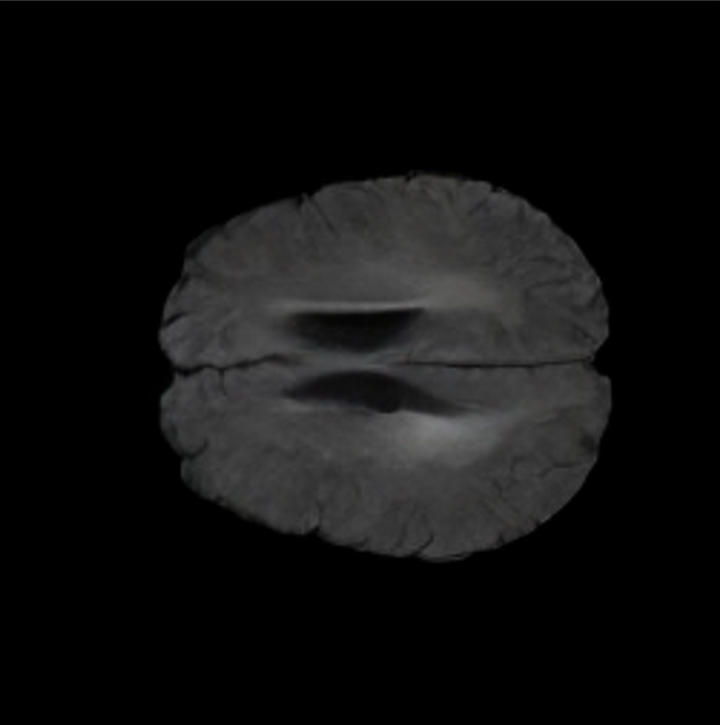

Brain Volumes Preservation. The generated MRIs by our X-Diffusion retain almost the exact same average brain volume vs. of the real MRIs.

Tumour Information Preservation. For the brain tumor segmentation, we use a Swin UNETR model[28, 70], trained with random rotation, and intensity as data augmentation. On the test set with human ground-truth annotations (), the brain volumes generated from single slice input preserve the volume of the different tumour components (paired t-test, for all 3 classes). In Figure 4, we highlight the tumor profiles of the generated MRIs compared to the ground truth tumour profile. The real MRI Dice score in the test set is 85.15 while the generated MRIs from a single slice have a dice score of 83.09. This shows how the generated MRIs indeed preserve the tumor information and can act as an affordable and informative pseudo-MRI, before conducting an actual costly MRI examination in hospitals. More detailed results are provided in supplementary material.

The comparison of generated MRIs versus reference MRIs suggest a nearly perfect preservation of brain volume (in mm3) with median volume of reference MRIs of versus generated MRIs (see an example of brain generation in Figure II).